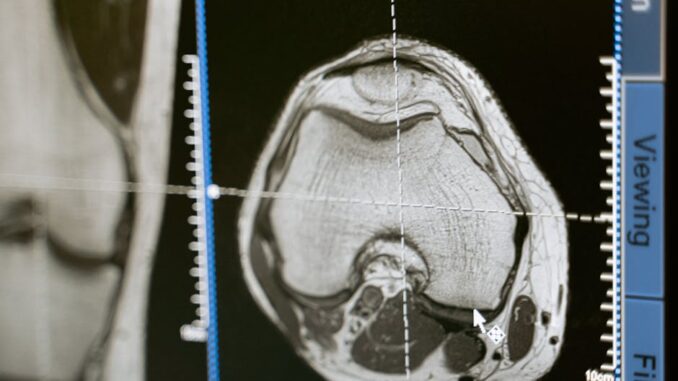

THz imaging and spectroscopy hold great promise for biomedical applications, including disease diagnostics, drug discovery, and personalized medicine. The non-ionizing nature of THz radiation makes it safe for imaging biological tissues. THz imaging can be used to differentiate between healthy and diseased tissues based on their different dielectric properties in the THz range. For example, THz imaging has shown potential for detecting skin cancer, breast cancer, and other types of cancer. THz-TDS can also be used to monitor the hydration levels of skin, providing valuable information for dermatological applications. In addition, THz spectroscopy can be used to study the interaction of drugs with biological molecules, accelerating the drug discovery process. The ability to probe biological materials in a non-destructive and label-free manner makes THz technology an attractive tool for biomedical research. However, the high water content of tissue means the penetration depth of THz radiation is severely limited. This can be overcome by collecting reflected THz waves instead of transmitted waves.